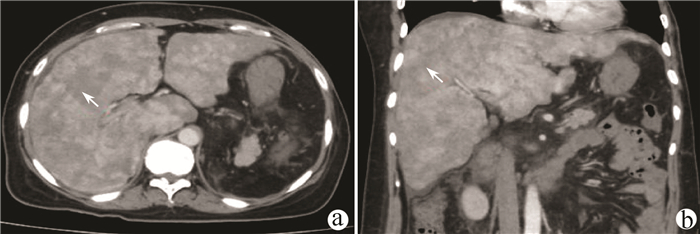

Jaundice and portal hypertension caused by hepatic epithelioid hemangioendothelioma: A case report